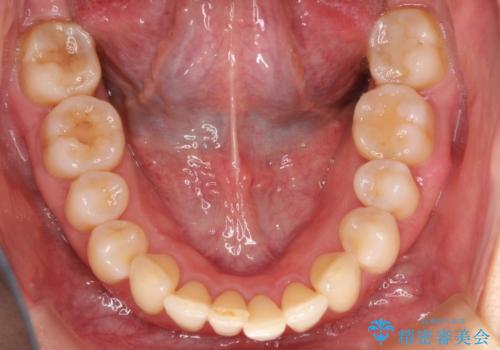

再矯正をインビザラインで目立たず手軽に

- 以前矯正をしていたが、わずかに後戻りをしてしまったのを主訴に来院されました。

装置はなるべくつけたくないとのことで、インビザラインにて治療することとなりました。

以前ワイヤー矯正をされていた方は、装置をつけての再矯正を希望されない方もいます。

その場合にインビザラインをお勧めさせていただいております。

後戻りがわずかな場合は、期間も短くて済む場合があります。